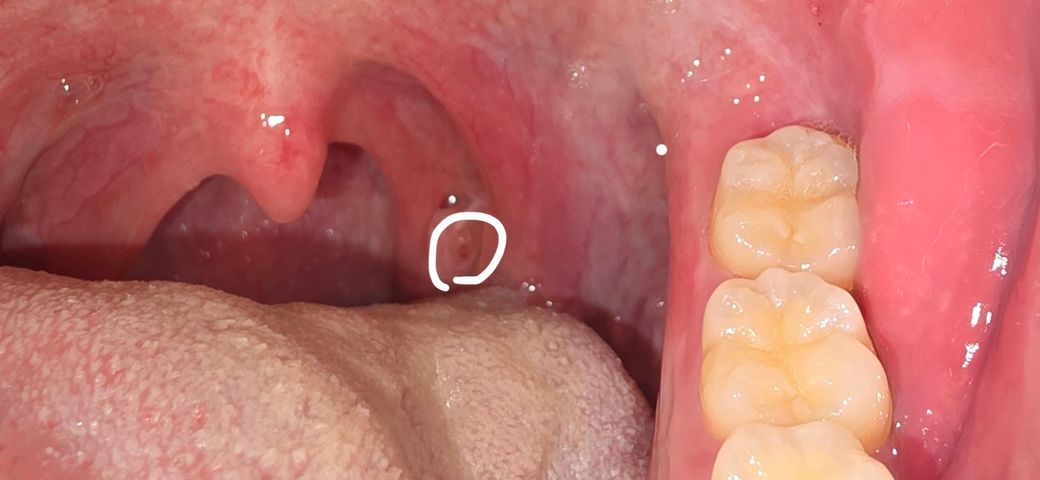

왼쪽 편도에 작은 빨간 점이 생겼습니다.

최근에 편도결석같은 이물질도 나오고 좀 아파서 봤더니 작은 붉은점에 가운데가 하얗습니다. 편도염인가요 궁금합니다. 따로 열나거나 하지는않지만 가렵기도하고 그럽니다.

• 1번 째 사진